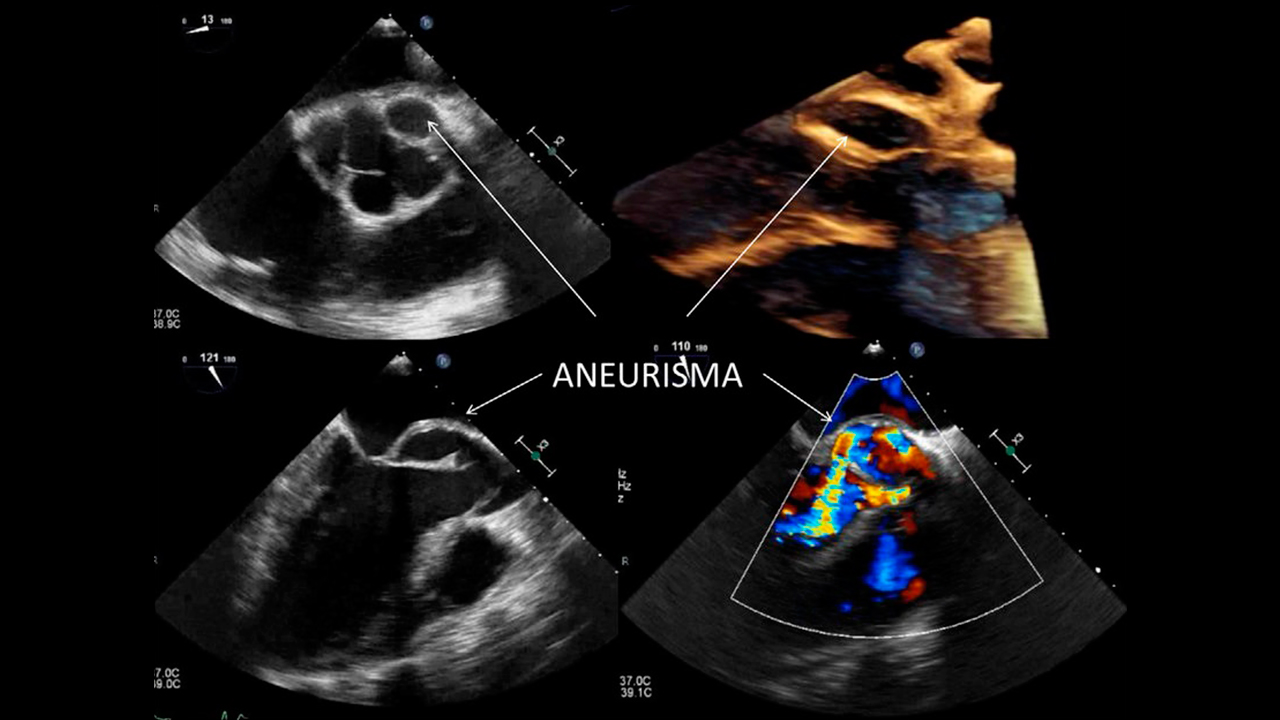

Ecocardiograma Transtorácico y Transesofágico

El ecocardiograma transtorácico no provoca molestias y no necesita preparación, consiste en la colocación externa del transductor en la pared torácica para ir observando las diferentes partes del corazón. La ecocardiografía transesofágica se realiza con una sonda a través de la boca y requiere sedación.